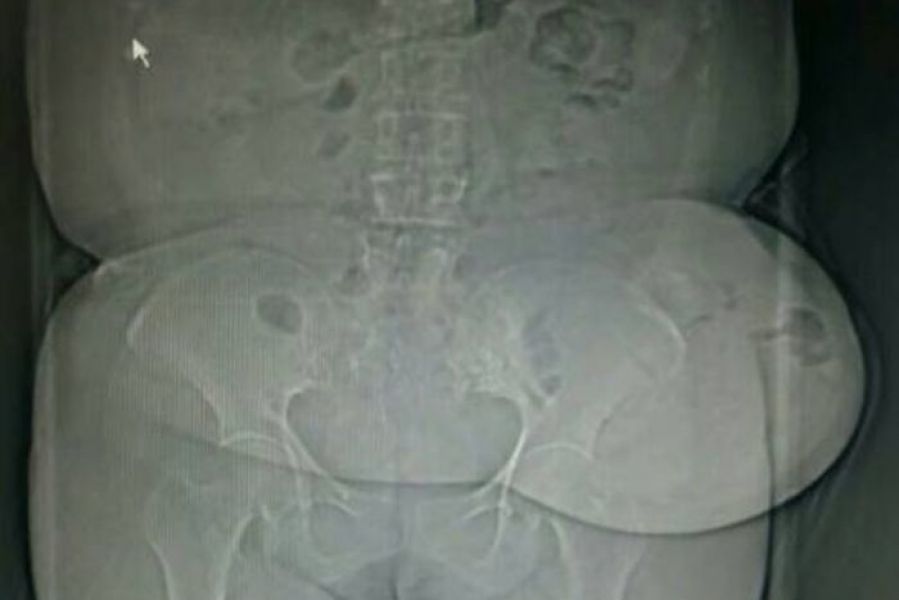

患者入住普五科后,完善相关检查,腹部CT提示左侧造口旁巨大疝块凸出,局部缺损达到13厘米,部分小肠肠管位于正常腹腔之外(又称为“第二腹腔”),符合巨大疝的特点(直径超过10厘米)。

入院时的影像学检查——可见左侧腹腔巨大肿块影凸出